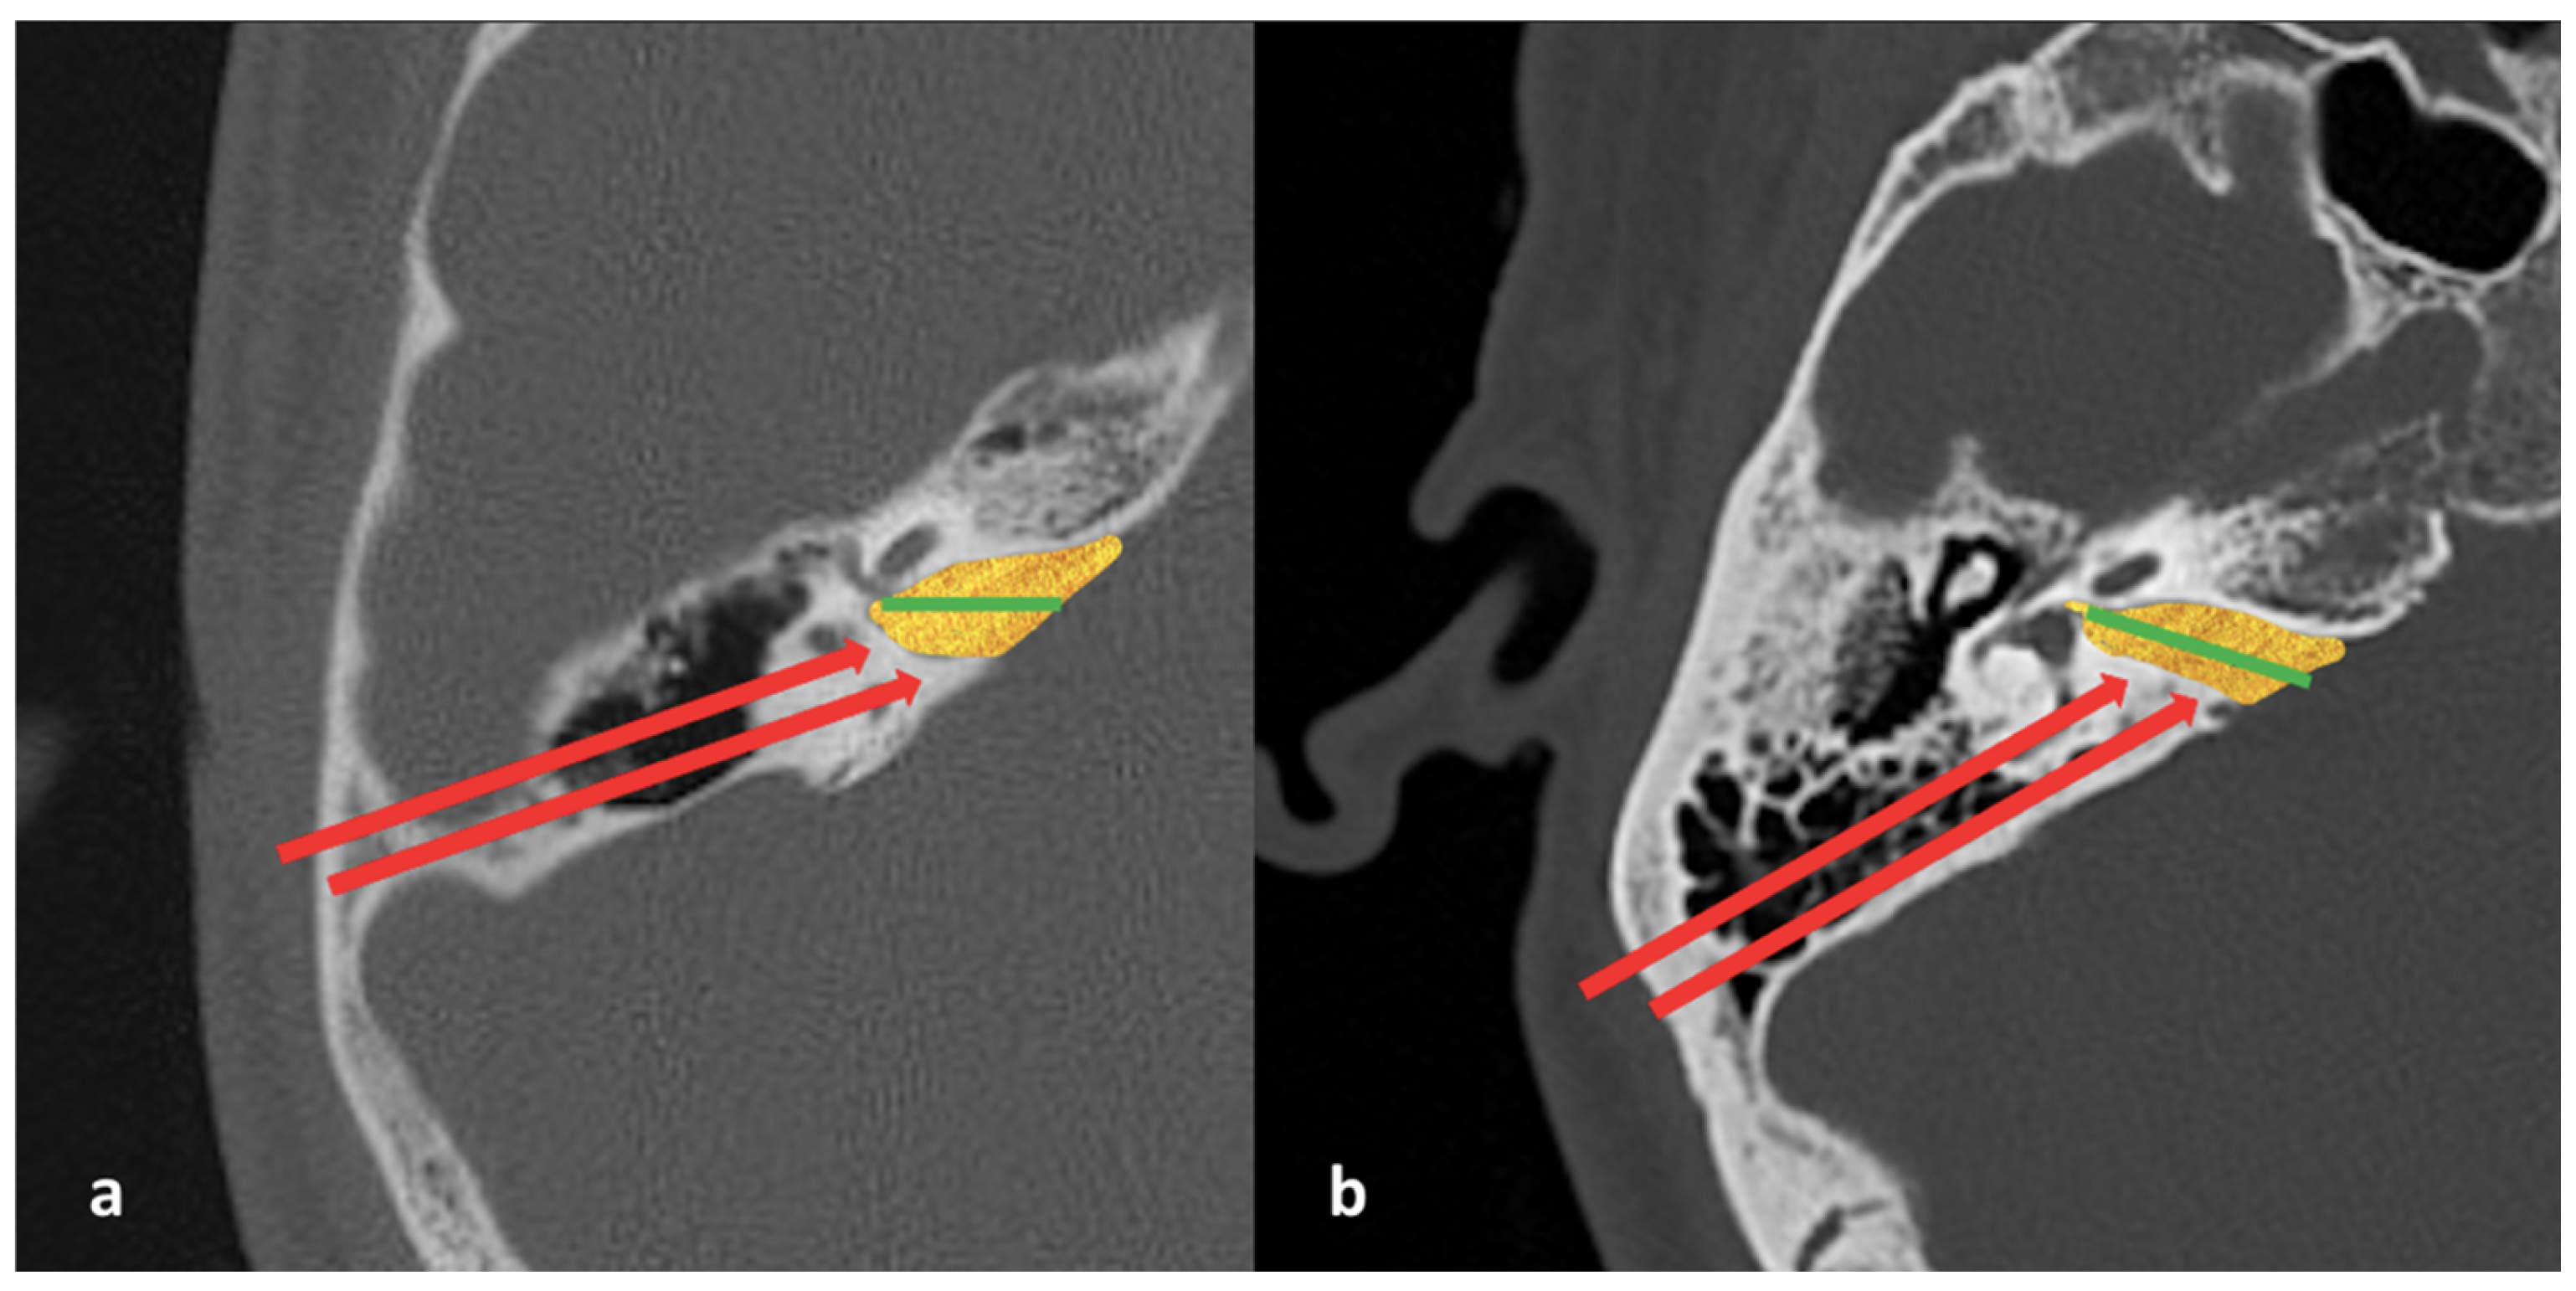

- Bilateral IAM inlet diameter: the distance between the anterior and posterior walls at the most medial part of the IAM (Figure 2);

- Bilateral IAM length: the distance between the most lateral point of the IAM and the midpoint of the inlet diameter (Figure 2);

- Bilateral IAM mid-diameter: the distance measured at the midpoint of the IAM length, parallel to the inlet diameter (Figure 2);